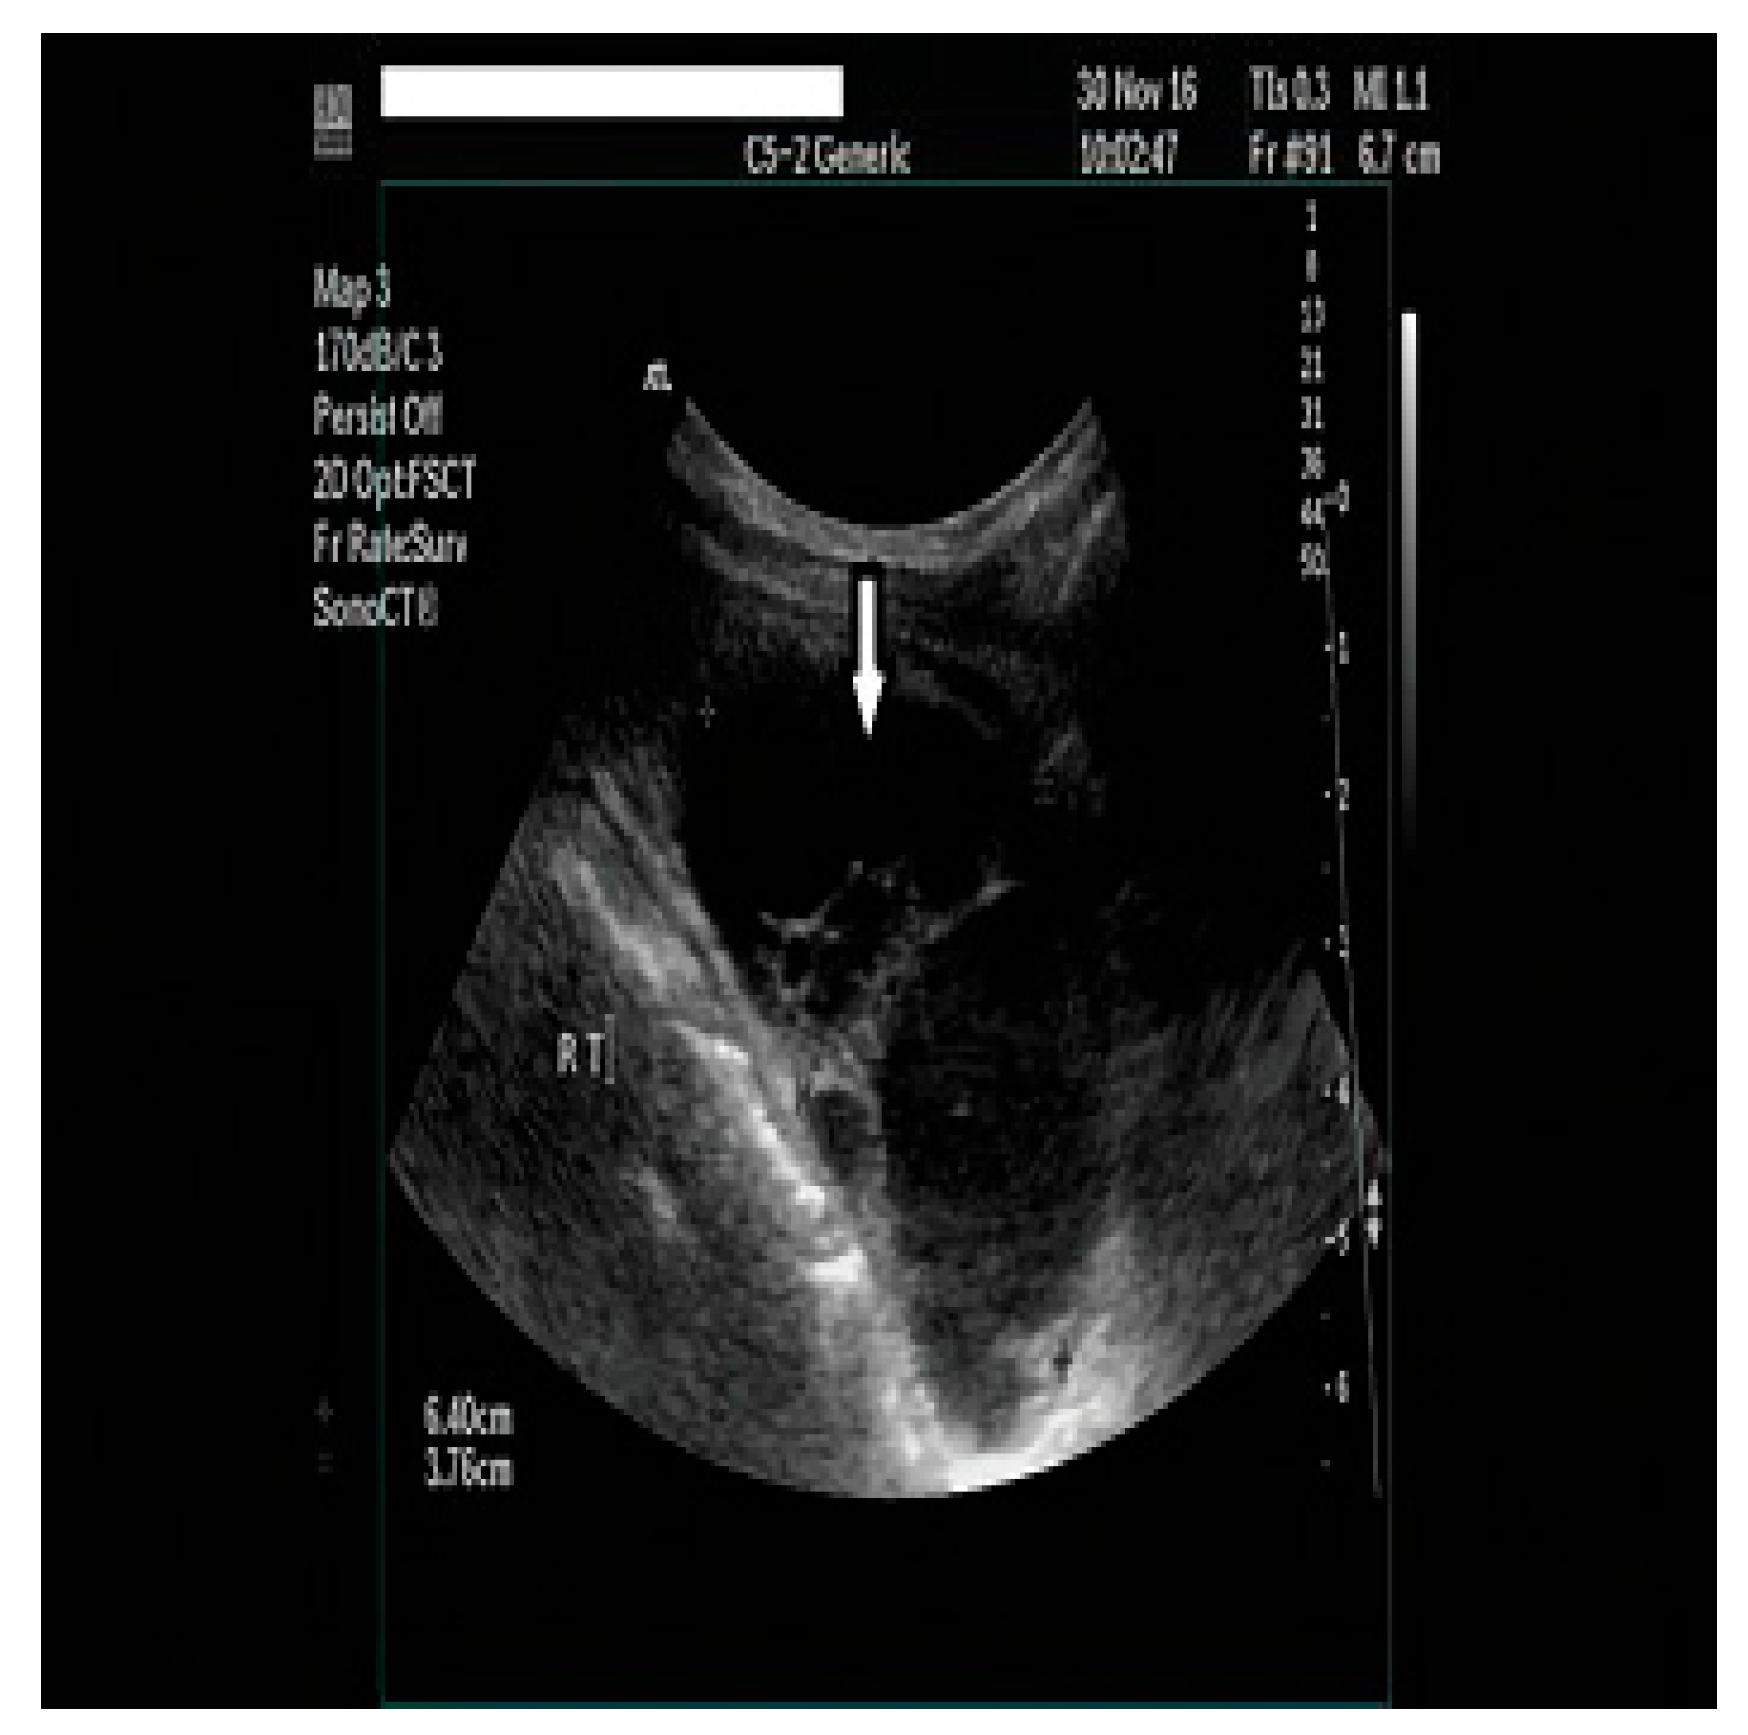

2.1. Diagnostic Assessment